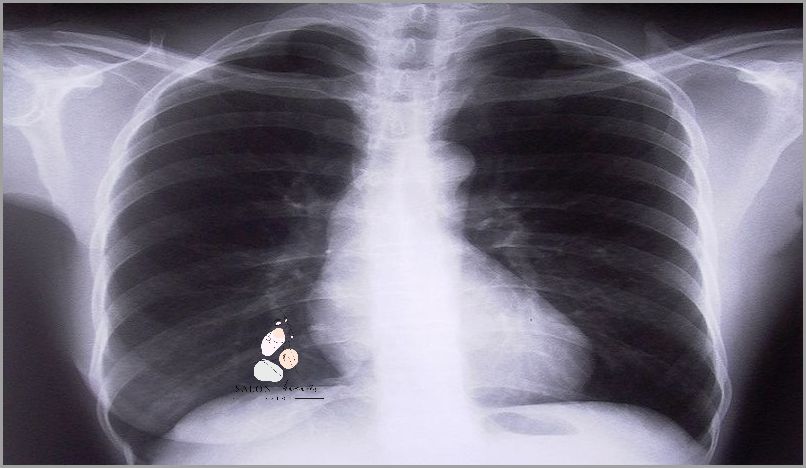

Proces leczenia rozpoczyna się od postawienia diagnozy – diagnoza przeprowadzana jest zazwyczaj na podstawie badań laboratoryjnych, a także zdjęć RTG, tomografii komputerowej lub rezonansu magnetycznego. Jeśli potwierdzone zostanie istnienie raka, lekarz przepisze odpowiednie leczenie, które może obejmować chirurgię, radioterapię i/lub chemioterapię.